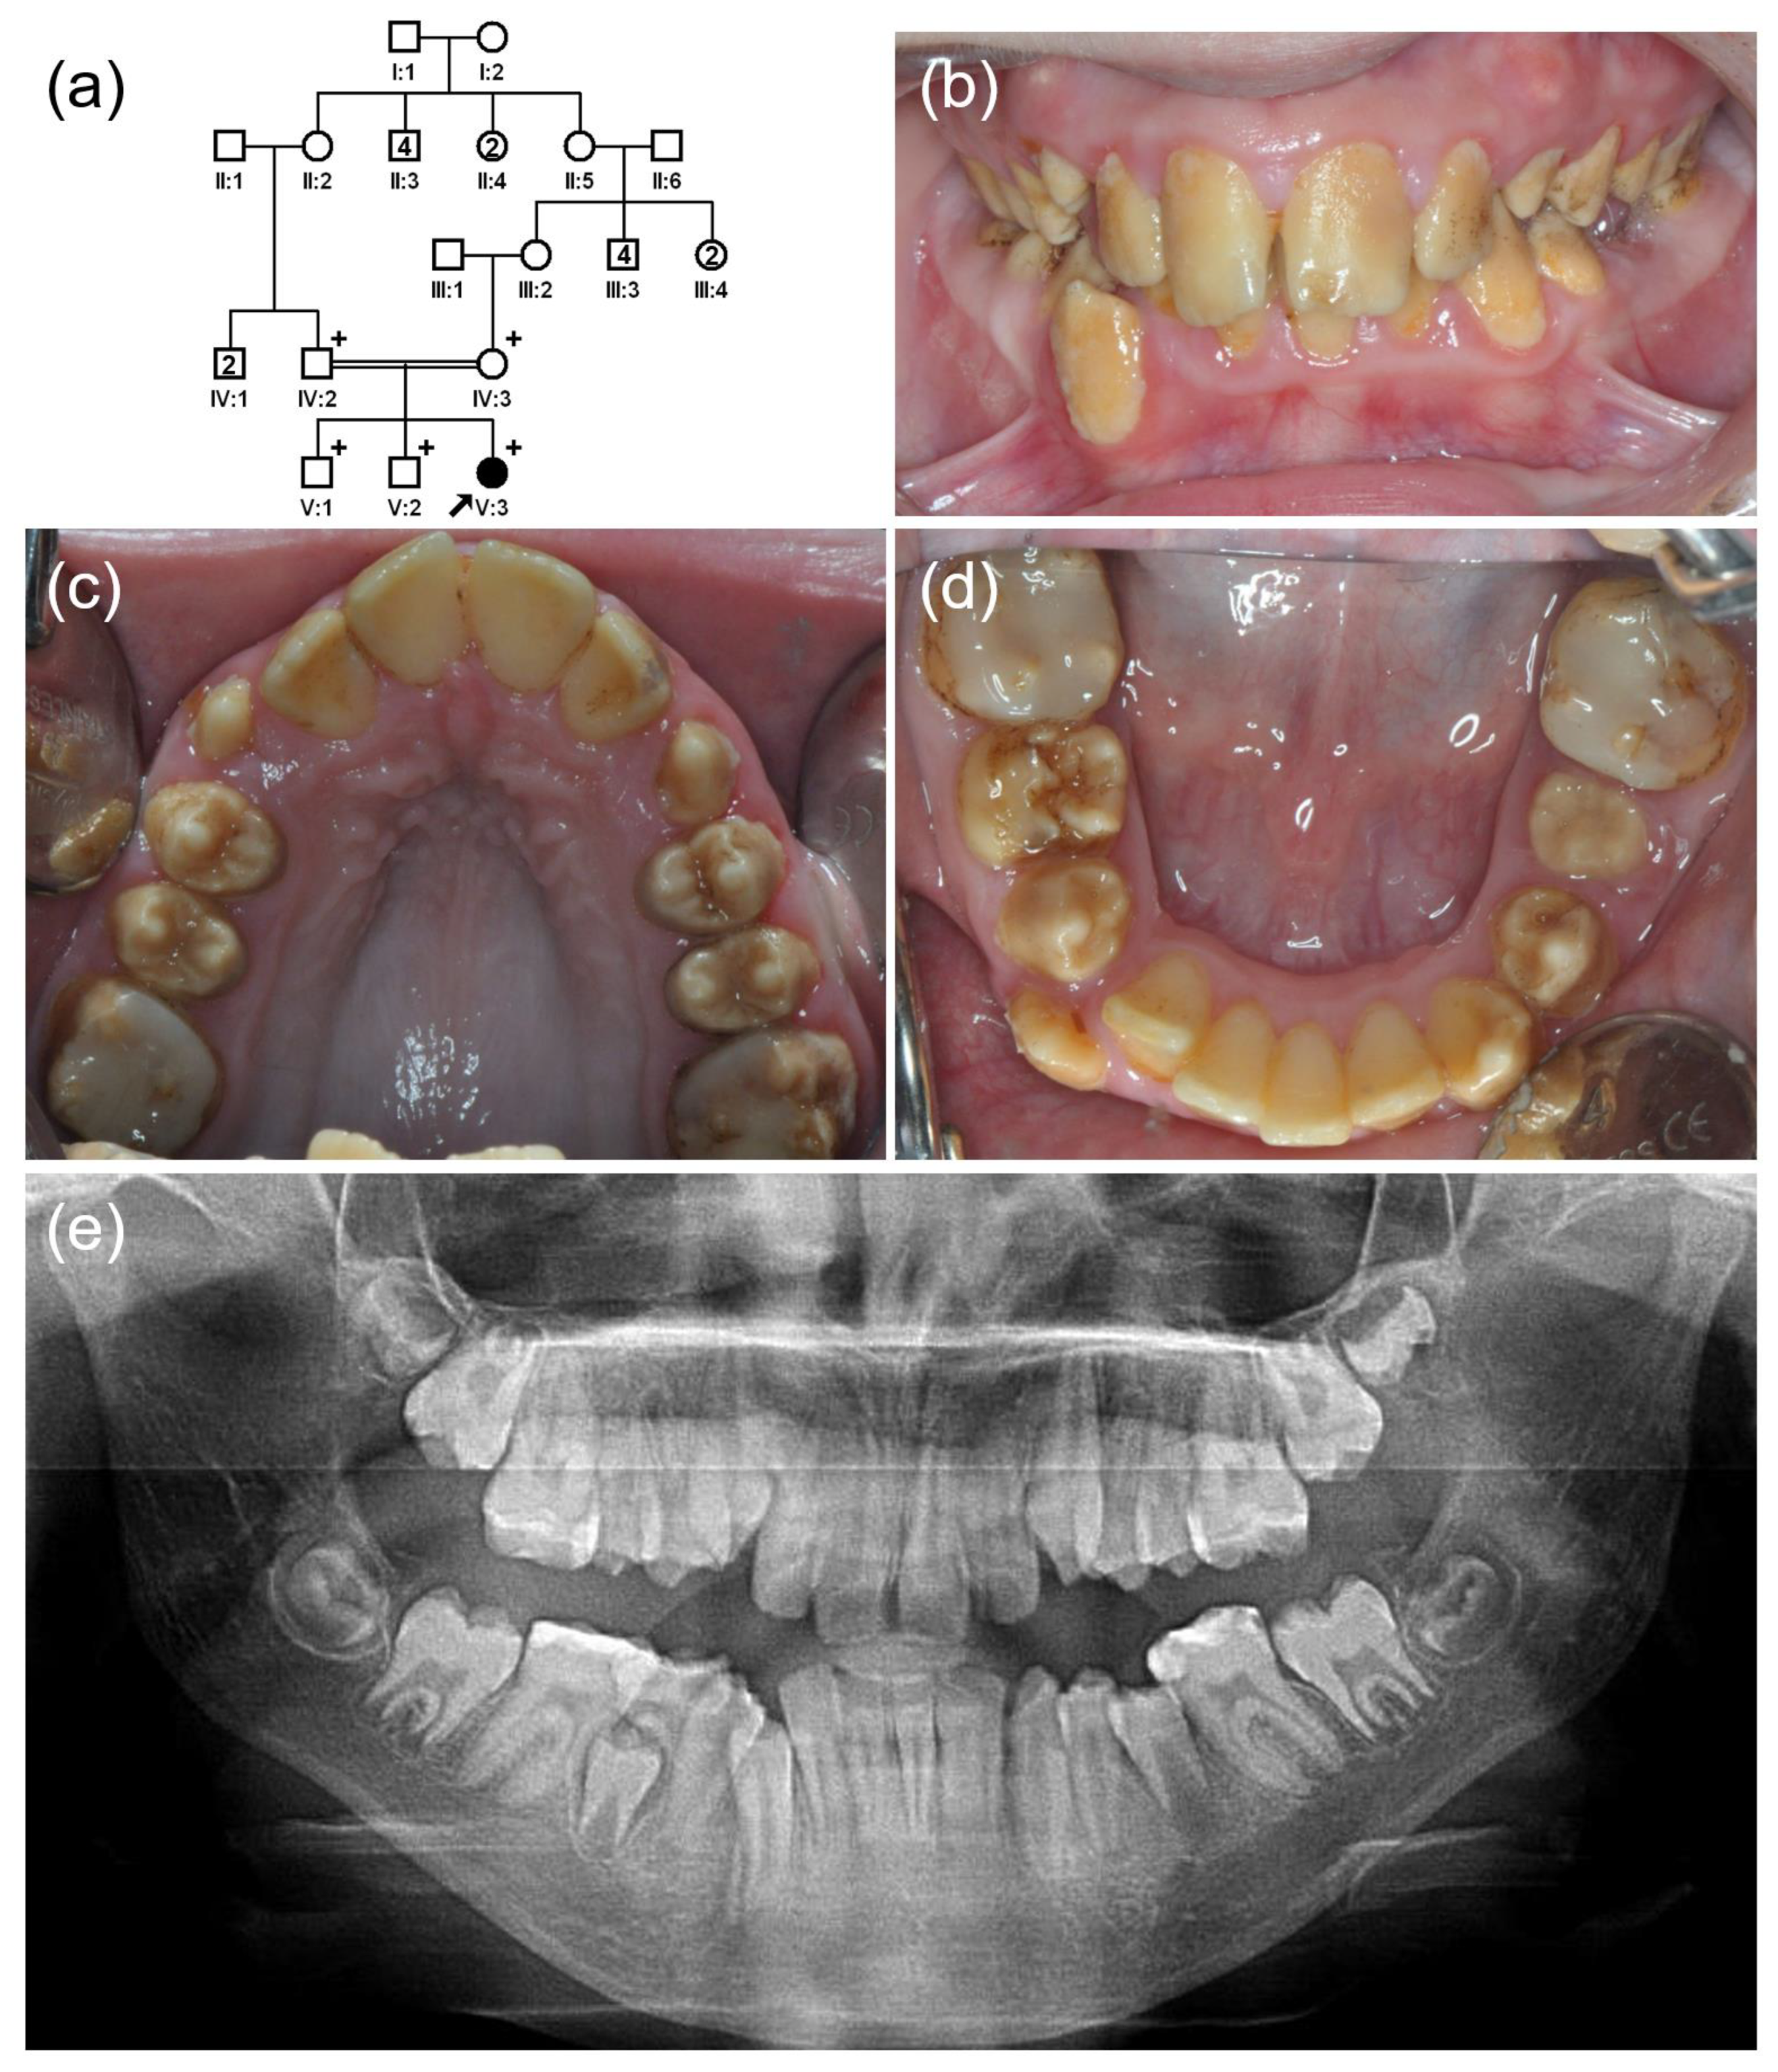

3.2. Family 2